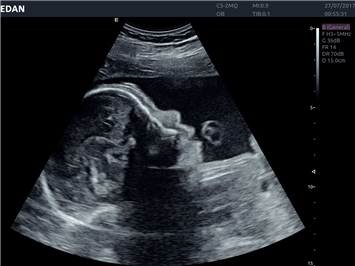

• Автоматизированные измерения в акушерстве

• Акушерства и гинекологии

• Педиатрии